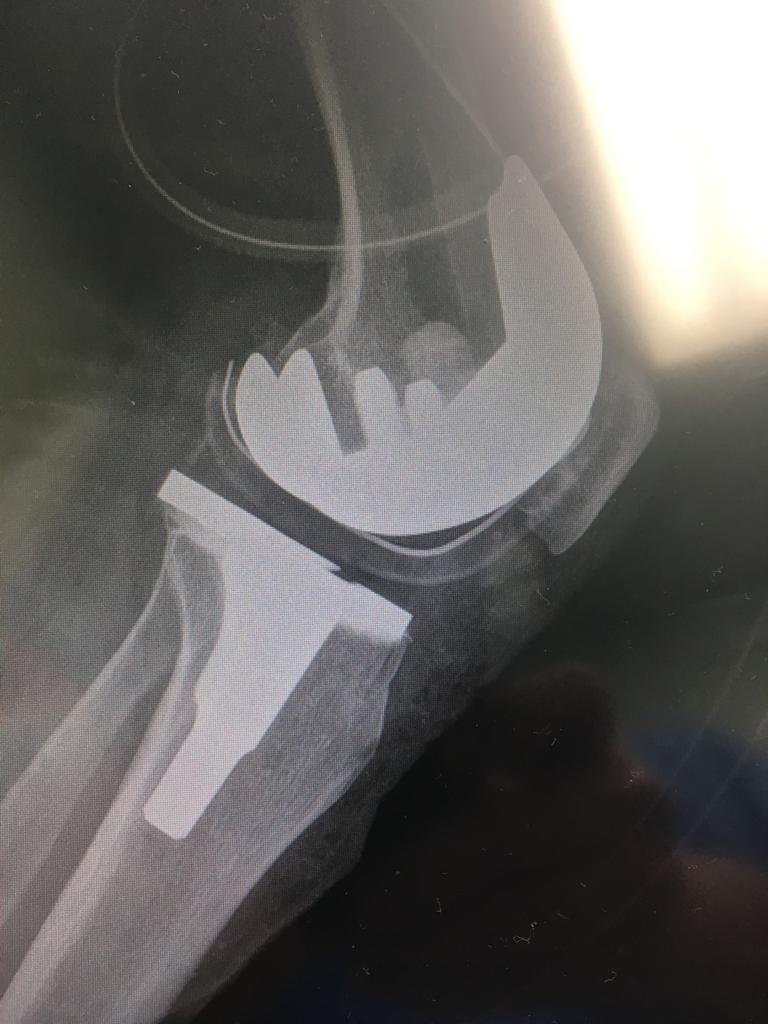

Source: doctorsandoval.cl

Enceinte va décider Crasseux operacion protesis de rodilla Alcool

Source: www.alexmccullochart.com.au